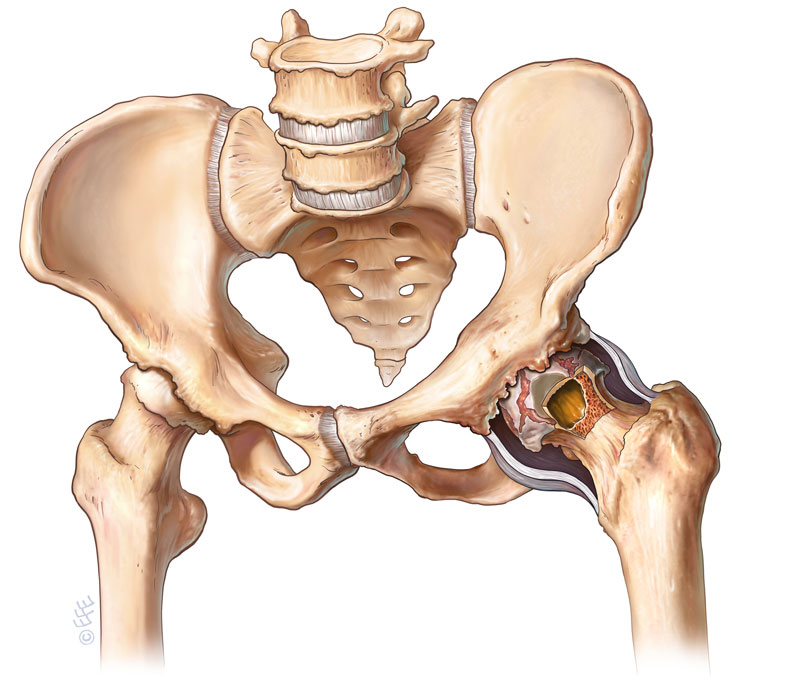

(Figure 1. Cartilage damage seen in Osteoarthritis)

Arthritis of the hip joint is a common condition. It usually affects middle-age and older people resulting in over 40,000 hip replacements being performed in Australia per year to relieve sufferers of their pain. It comes about when the cartilage which overlies the femur (leg) bone or lines the acetabulum (pelvic) bone wears out and exposes “bone on bone” articulation resulting in pain, stiffness and disability.

Many forms of arthritis have been described. Osteoarthritis is the most common form characterized by the break-down of the joint’s cartilage. The exact cause of osteoarthritis is unknown but it may occur in families (genetic predisposition), post-injury or as a result of an infection in the joint.